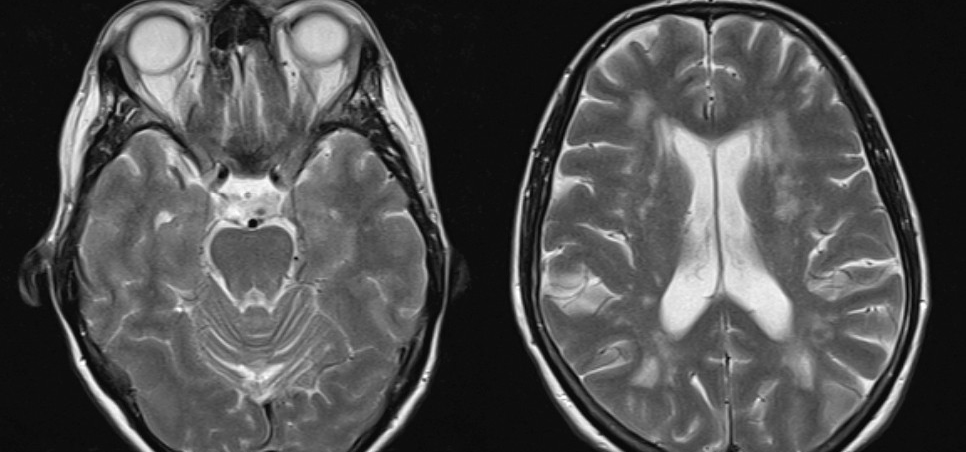

Flere populasjonsbaserte studier med MR-undersøkelser har vist forhøyet forekomst av subkliniske infarkter hos personer med migrene, spesielt migrene med aura (17). I enkelte studier har man også funnet en forhøyet forekomst av uspesifikke hvitsubstanslesjoner i hjernen, mens andre ikke har gjenfunnet dette (18, 19) (fig 2). Man har imidlertid ikke kunnet påvise noen sammenheng mellom slike tilfeldig oppdagede radiologiske endringer og redusert kognitiv funksjon hos personer med migrene, og den kliniske betydningen av slike funn er usikker (20).